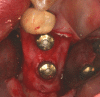

Peri-implant inflammations represent serious diseases after dental implant treatment, which affect both the surrounding hard and soft tissue. Due to prevalence rates up to 56%, peri-implantitis can lead to the loss of the implant without multilateral prevention and therapy concepts. Specific continuous check-ups with evaluation and elimination of risk factors (e.g. smoking, systemic diseases and periodontitis) are effective precautions. In addition to aspects of osseointegration, type and structure of the implant surface are of importance. For the treatment of peri-implant disease various conservative and surgical approaches are available. Mucositis and moderate forms of peri-implantitis can obviously be treated effectively using conservative methods. These include the utilization of different manual ablations, laser-supported systems as well as photodynamic therapy, which may be extended by local or systemic antibiotics. It is possible to regain osseointegration. In cases with advanced peri-implantitis surgical therapies are more effective than conservative approaches. Depending on the configuration of the defects, resective surgery can be carried out for elimination of peri-implant lesions, whereas regenerative therapies may be applicable for defect filling. The cumulative interceptive supportive therapy (CIST) protocol serves as guidance for the treatment of the peri-implantitis. The aim of this review is to provide an overview about current data and to give advices regarding diagnosis, prevention and treatment of peri-implant disease for practitioners.